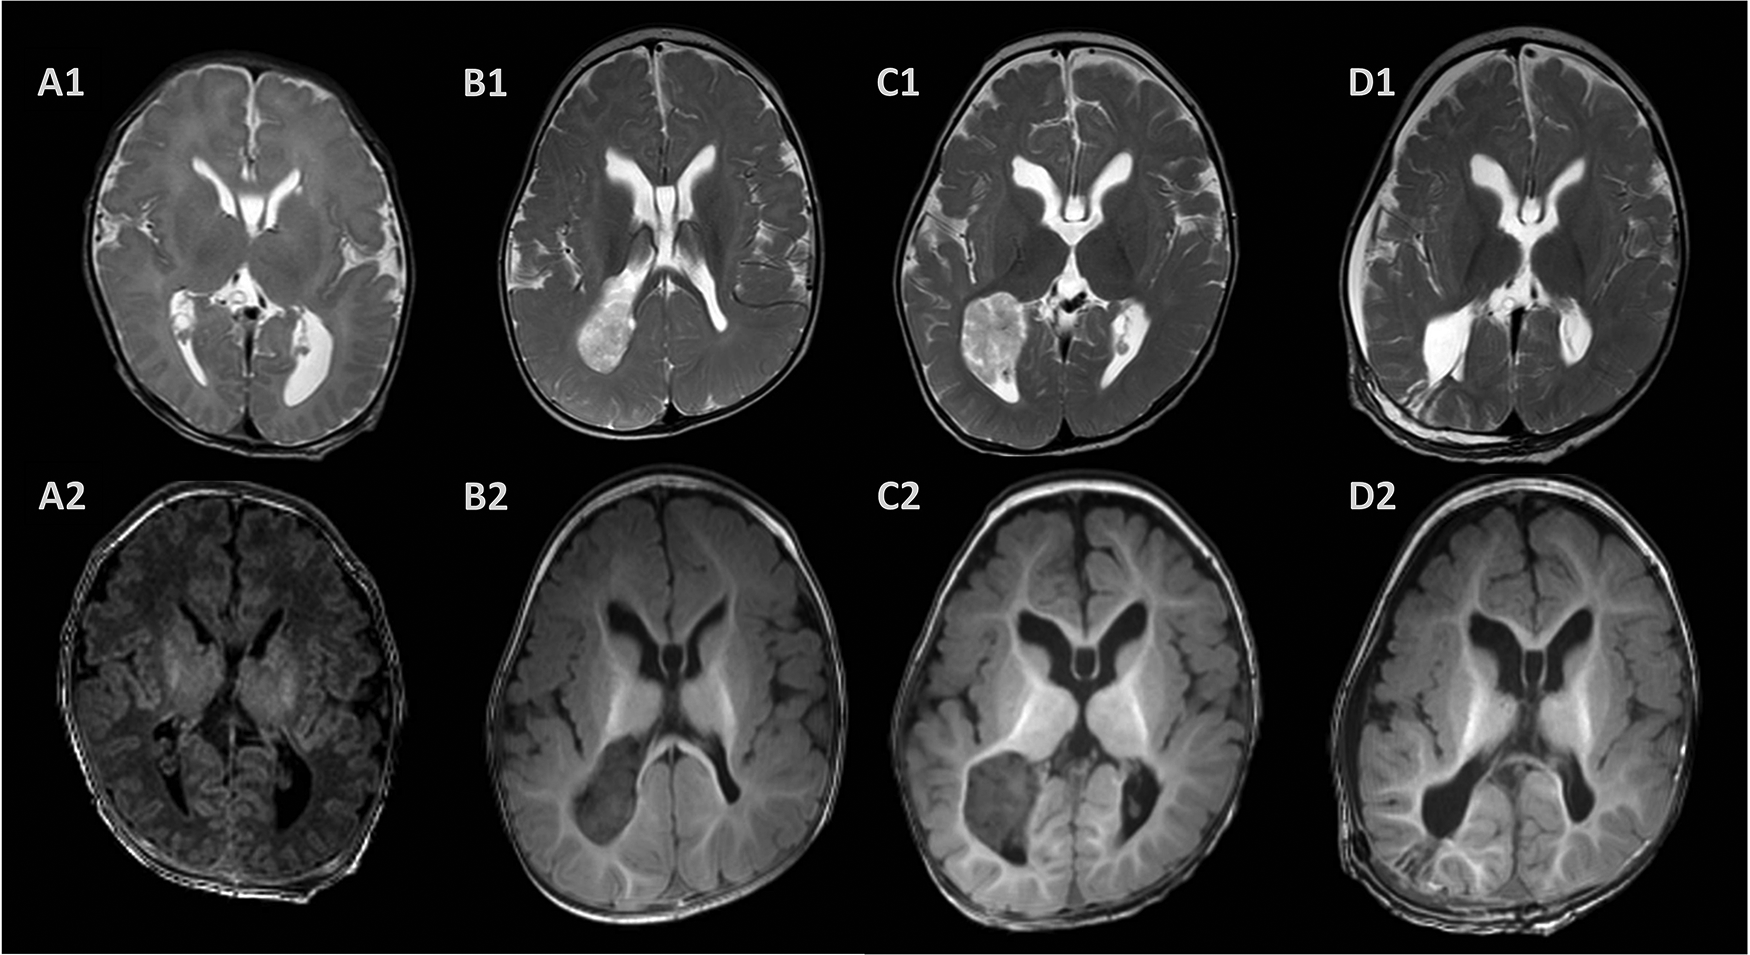

Figure 3

Postnatal magnetic resonance images. The brain MRI showed dilated ventricles, corpus callosum agenesis, and subependymal pseudocyst 3 days after birth (A). A large mass located in the posterior horn of the right ventricle with T2 heterogeneously hyperintense and T1 hypointense at 6 months (B) and 10 months (C) after birth with progression. T2- and T1-weighted images showed a Normal appearing choroid plexus and porencephalic cavity 2 weeks after surgery (D).

Due to the evaluation of the fetal ventriculomegaly, the brain MRI 3 days after birth showed a dilated left ventricle, corpus callosum agenesis, and subependymal pseudocyst. In addition, the cranial ultrasound provided the same results at the age of 3 days, 1 month, and 3 months. We performed a brain MRI scan after the diagnosis of infantile epileptic spasms syndrome. However, a large mass in the posterior horn of the right lateral ventricle with T2 heterogeneously hyperintense and T1 hypointense was observed in the brain MRI scan and considered to be a CPP (Figure 3). A large mass was removed through a right parietal craniotomy and the resected tissue was received in fragments aggregating to 2.5 cm × 2.0 cm × 2.0 cm. Histopathologic examination and immunoperoxidase staining showed the mass was a CPP.